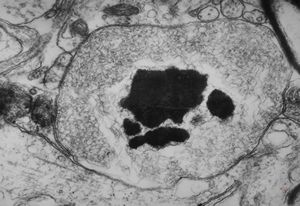

M,10y. | herpetic encephalitis